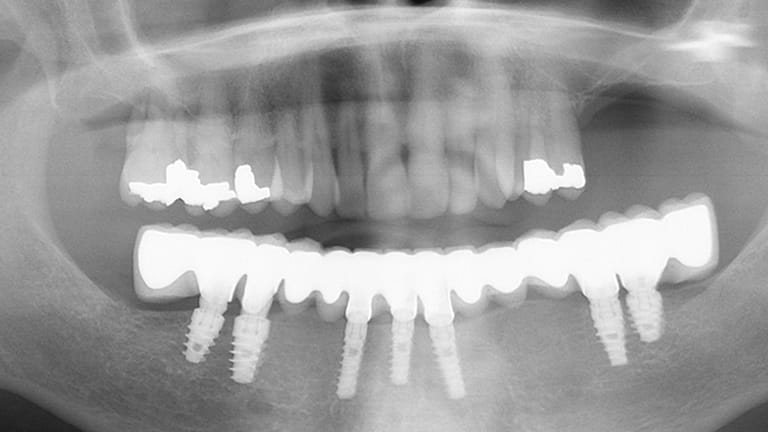

Dental implants are a titanium "root" which can be placed into the jawbone. Once integrated with your bone, the implant can be used to support a crown, a bridge, or secure a complete denture. Dental implants may be used to eliminate partial plates and dentures. The success rates for dental implants are extremely high which is due in part to the fact that root-form implants are made of a biocompatible material, titanium.

Implant Full Arch

Below is a few examples of what DENTAL IMPLANTS can do for you and your smile!